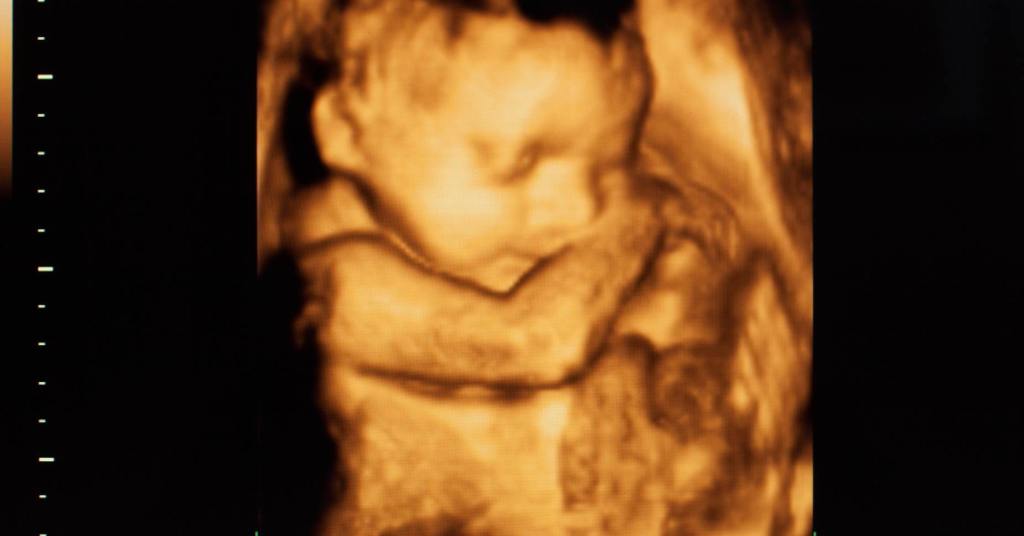

Independientemente de cómo sienten su propio nacimiento, están bien preparados para iniciar la vida en el exterior, pues en el vientre de su madre ya han practicado las funciones básicas para la supervivencia: succionar, tragar y las primeras respiraciones. Ahí estaba tan feliz y tenía todo lo que necesitaba.

Así es como al nacer el pequeño cuerpo se adapta en cuestión de segundos a las nuevas circunstancias fuera de la bolsa amniótica, donde se lo daban todo hecho y se encontraba bien protegido. Era el mejor sitio para crecer.